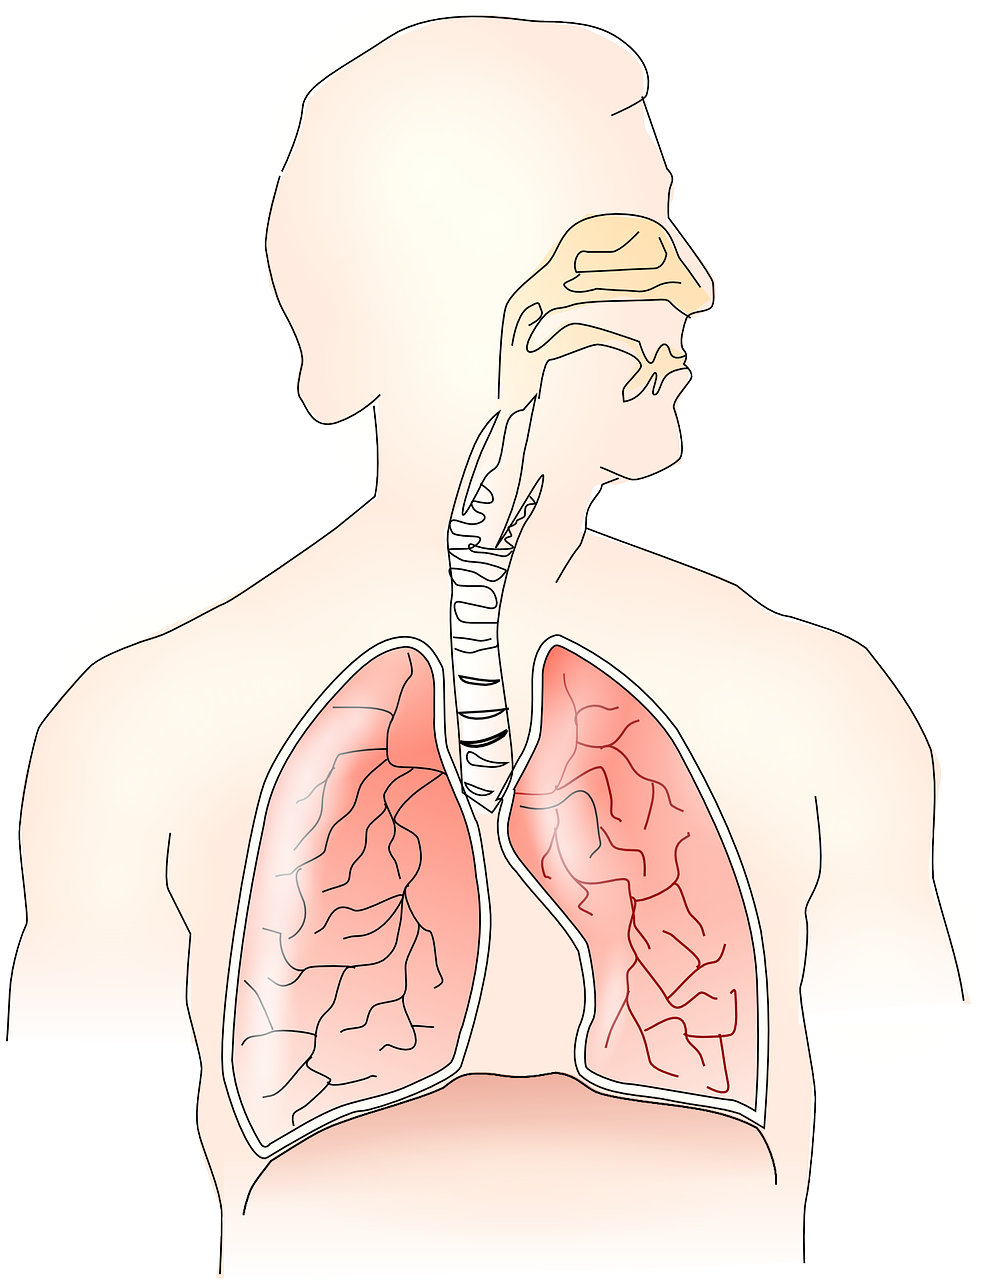

Oksijen vücudumuza solunum sistemi organlarıyla alınır.

Vücudumuzun dışarıdan oksijen alıp vücutta

oluşan karbondioksidi dışarı vermesine soluk alıp verme denir. Soluk alıp verme sırasında

görevli yapı ve organların oluşturduğu sistem solunum sistemi olarak adlandırılır. Solunum

sisteminin temel görevi, vücudun dışarıdan oksijen almasını sağlamak ve vücutta oluşan karbondioksidi dışarıya vermektir.

BURUN

Hava giriş ve çıkışı gerçekleşir.

Yapısında kıllar, kılcal kan damarları ve mukus salgısı üreten tabaka bulunur. Burundaki kıllar ve mukus, havayla gelen toz parçalarını tutar.

Mukus havayı nemlendirir. Kılcal kan damarları ise havayı ısıtır.

YUTAK

Ağız ve burun boşluğuyla yemek ve soluk borusunun birleştiği yerdir. Burun yoluyla alınan hava yutağa geçer.

GIRTLAK

Yutak ile soluk borusu arasında yer alır. Yutaktan gelen havayı soluk borusuna iletir. Burada sesin oluşmasını sağlayan ses telleri bulunur.

SOLUK BORUSU

Gırtlaktan gelen havanın akciğerlere ulaşmasını sağlar. Üst üste dizilmiş kıkırdak halkalardan oluşur. İç kısmını kaplayan bir zar vardır.

Bu zar kaygan ve yapışkan bir sıvı üreterek toz ve mikropları tutar. Tutulan toz, mikrop ve yabancı maddeler balgam olarak vücuttan dışarı atılır.

Bronş Ve Bronşcuklar

Soluk borusu akciğere girerken bronş adı verilen iki kola ayrılır.

Bronşlar akciğere girdikten sonra çok sayıda kollara ayrılır. Bu kolların her birine bronşçuk adı verilir. Bronşçukların ucunda alveol adı verilen hava keseleri bulunur.

AKCİĞER

Nefes alıp-verme yoluyla temiz havanın vücut içine alınmasını ve kirli havanın vücut dışına atılmasını sağlayan organlardır. Akciğerler, göğüs kafesi içinde yer alan pembe renkli, süngerimsi görünüşte organlardır. Akciğerler, sağ ve sol olmak üzere iki bölümden oluşur. Sol taraftaki akciğer, hemen altında kalp bulunduğu için daha küçüktür.

DİYAFRAM

Akciğerlerin çalışmasına yardımcı olan güçlü bir kastır. Diyafram, düzleşerek ya da kubbeleşerek hava giriş çıkışına yardımcı olur.

Akciğerlerin altında bulunan diyafram kası ve çevresindeki kaburgalar arası kaslar, soluk alıp verme esnasında kasılıp gevşer. Bu sayede akciğerler genişleyip daralır.